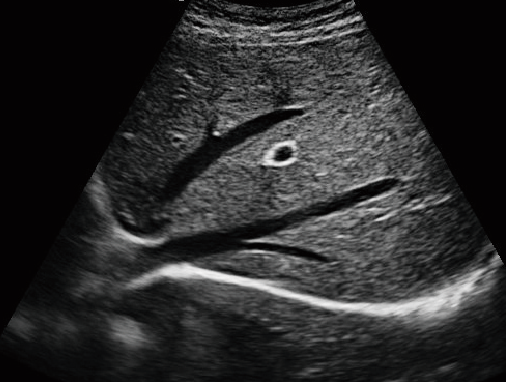

MU15便携笔记本式兽用B超机

动物宠物超声诊断仪

彩色多普勒动物超声诊断仪

·显示模式:B、B+B、4B、B+M、M、PW

·具有专业的动物产科软件包,分别是狗、猫、马、牛、羊

·适用于各种动物的临床腹部、胸腔,心脏、肌腱、小器官、眼球、生殖系统等的检查